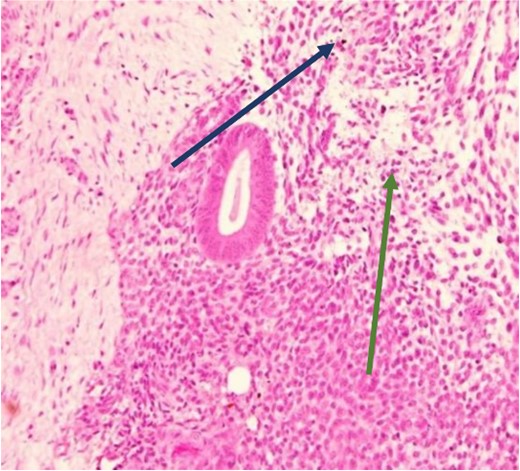

The mass was located in the subcutaneous tissue deep to the previous Pfannenstiel scar but did not invade the anterior rectus fascia. The mass was cleanly separated from the fascia and there was no invasion of the underlying muscle. During dissection, a few areas of the fascia were entered and repaired primarily. Pathology revealed endometriosis within a 4 × 3.5 × 2 cm mass with the closest margin of endometrial-like tissue measuring 2 mm from the specimen edge (Fig. 10a and b). During her postoperative visit 1 month later, the patient complained of some discomfort, yet her cyclical symptoms had resolved.

Proliferative endometrial gland (arrows) and stroma with hemorrhage in the lumen of the gland at 20× (a) and 40× (b) (H&E).